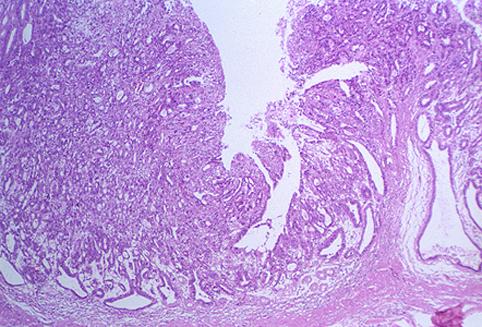

질환(병리주체)의 분류 악성 상피성종양/선암

부위(장기별) 위(부위)/전정

검사방법 마이크로

종양의 육안분류 0형(표재형)/IIa형(IIa+IIc)

종양의 최대경(밀리미터) 25~29

종양의 심달도 m